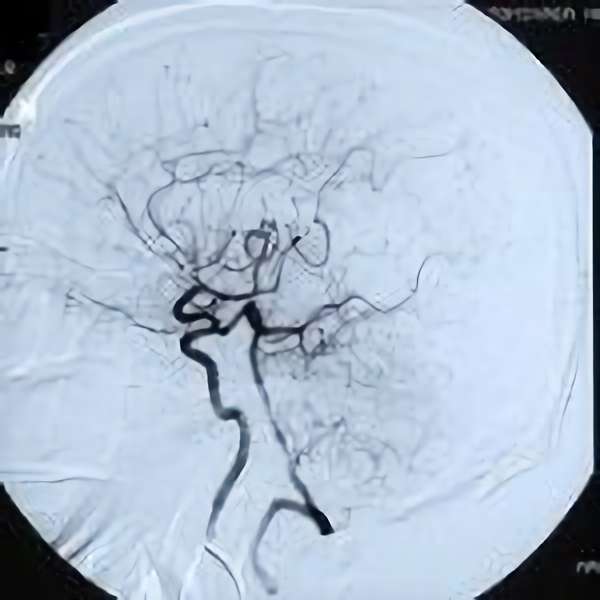

脳血管撮影

手術前

手術後